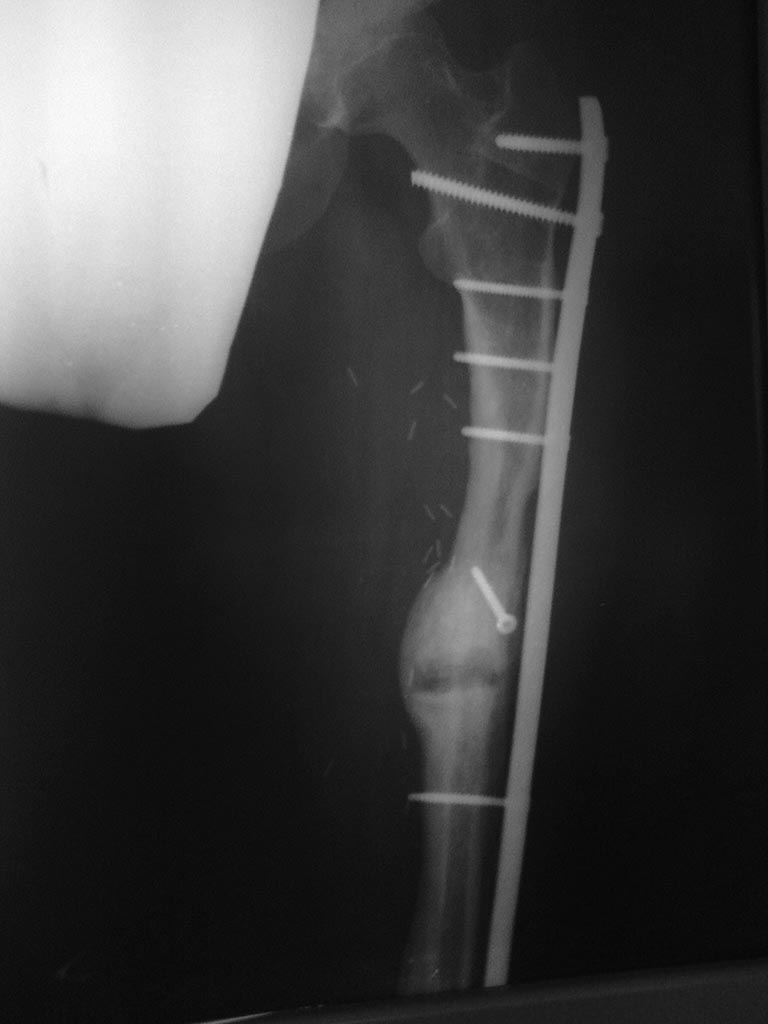

[Ortho] Саркома бедра

Продолжение истории. От  биопсии родственникиотказались, результат на

март (фото) на фоне лечения "Prolia"